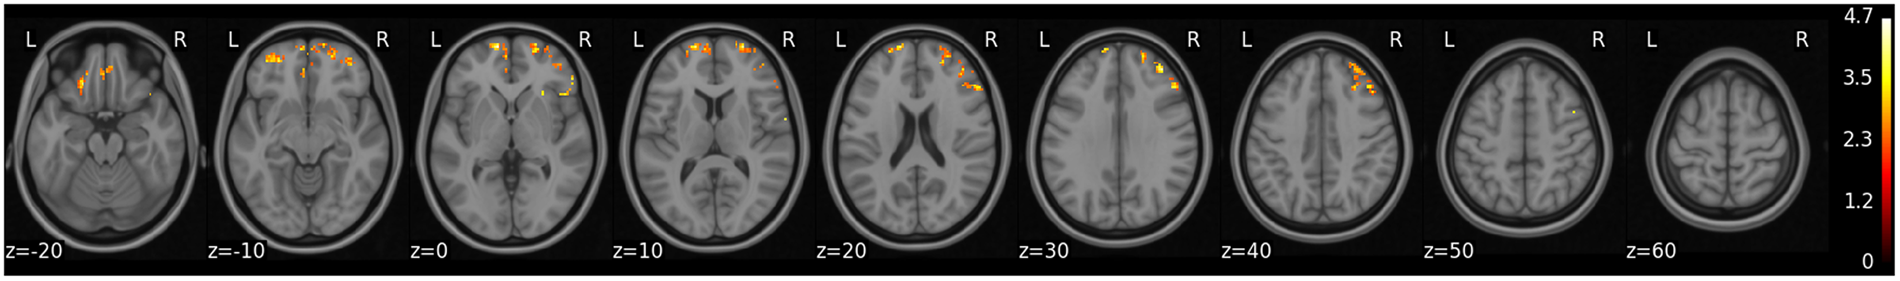

Figure 2

Voxel wide analysis of gmCBF for AD-PRS. Regional association between gmCBF and AD-PRS across all grey matter. All clusters that remain (red-yellow) reflect voxels that survived correction across the whole brain (using threshold free cluster enhancement) with permutation testing (N = 5000) (PFWE < 0.05). Color-bar represents regional t-statistic.